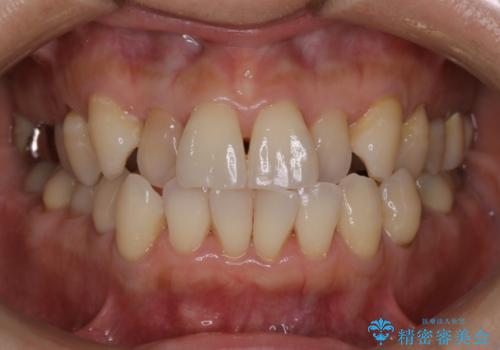

![[突き出た前歯を引っ込めたい] ワイヤー矯正とマウスピース矯正の併用治療の症例 治療前](https://seimitsushinbi.jp/wp/wp-content/uploads/2024/08/IMG_0066-500x350.jpg?v=1723179360)